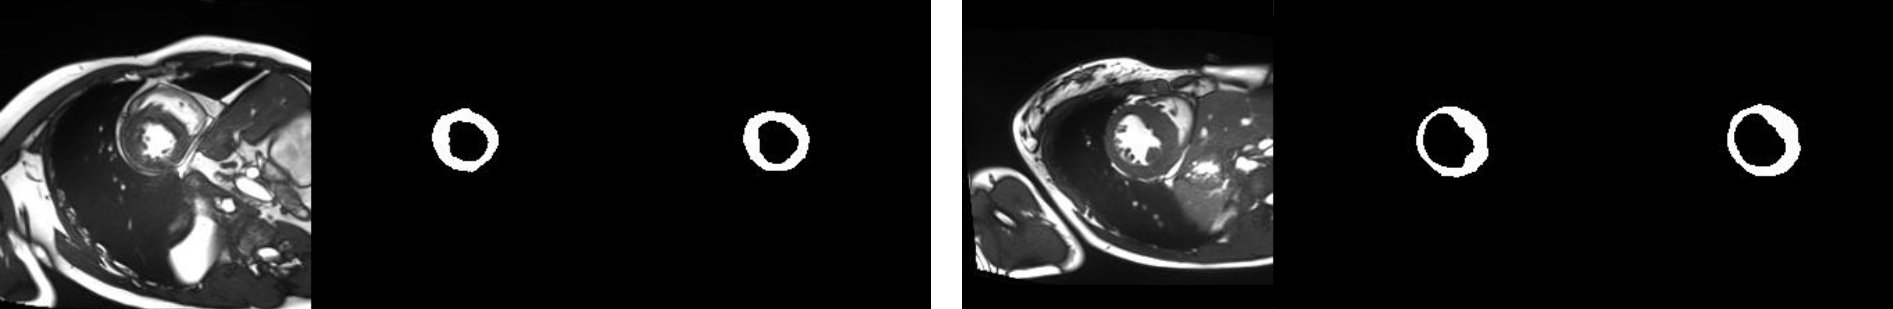

Refer to caption

Figure 4: Two examples of segmentation performance: input, prediction and ground truth.

The utility of a factorised representation becomes evident in semi-supervised learning. Qualitatively in Fig. 4 we can see that our method closely follows ground truth segmentation masks (example from ACDC held-out test set).